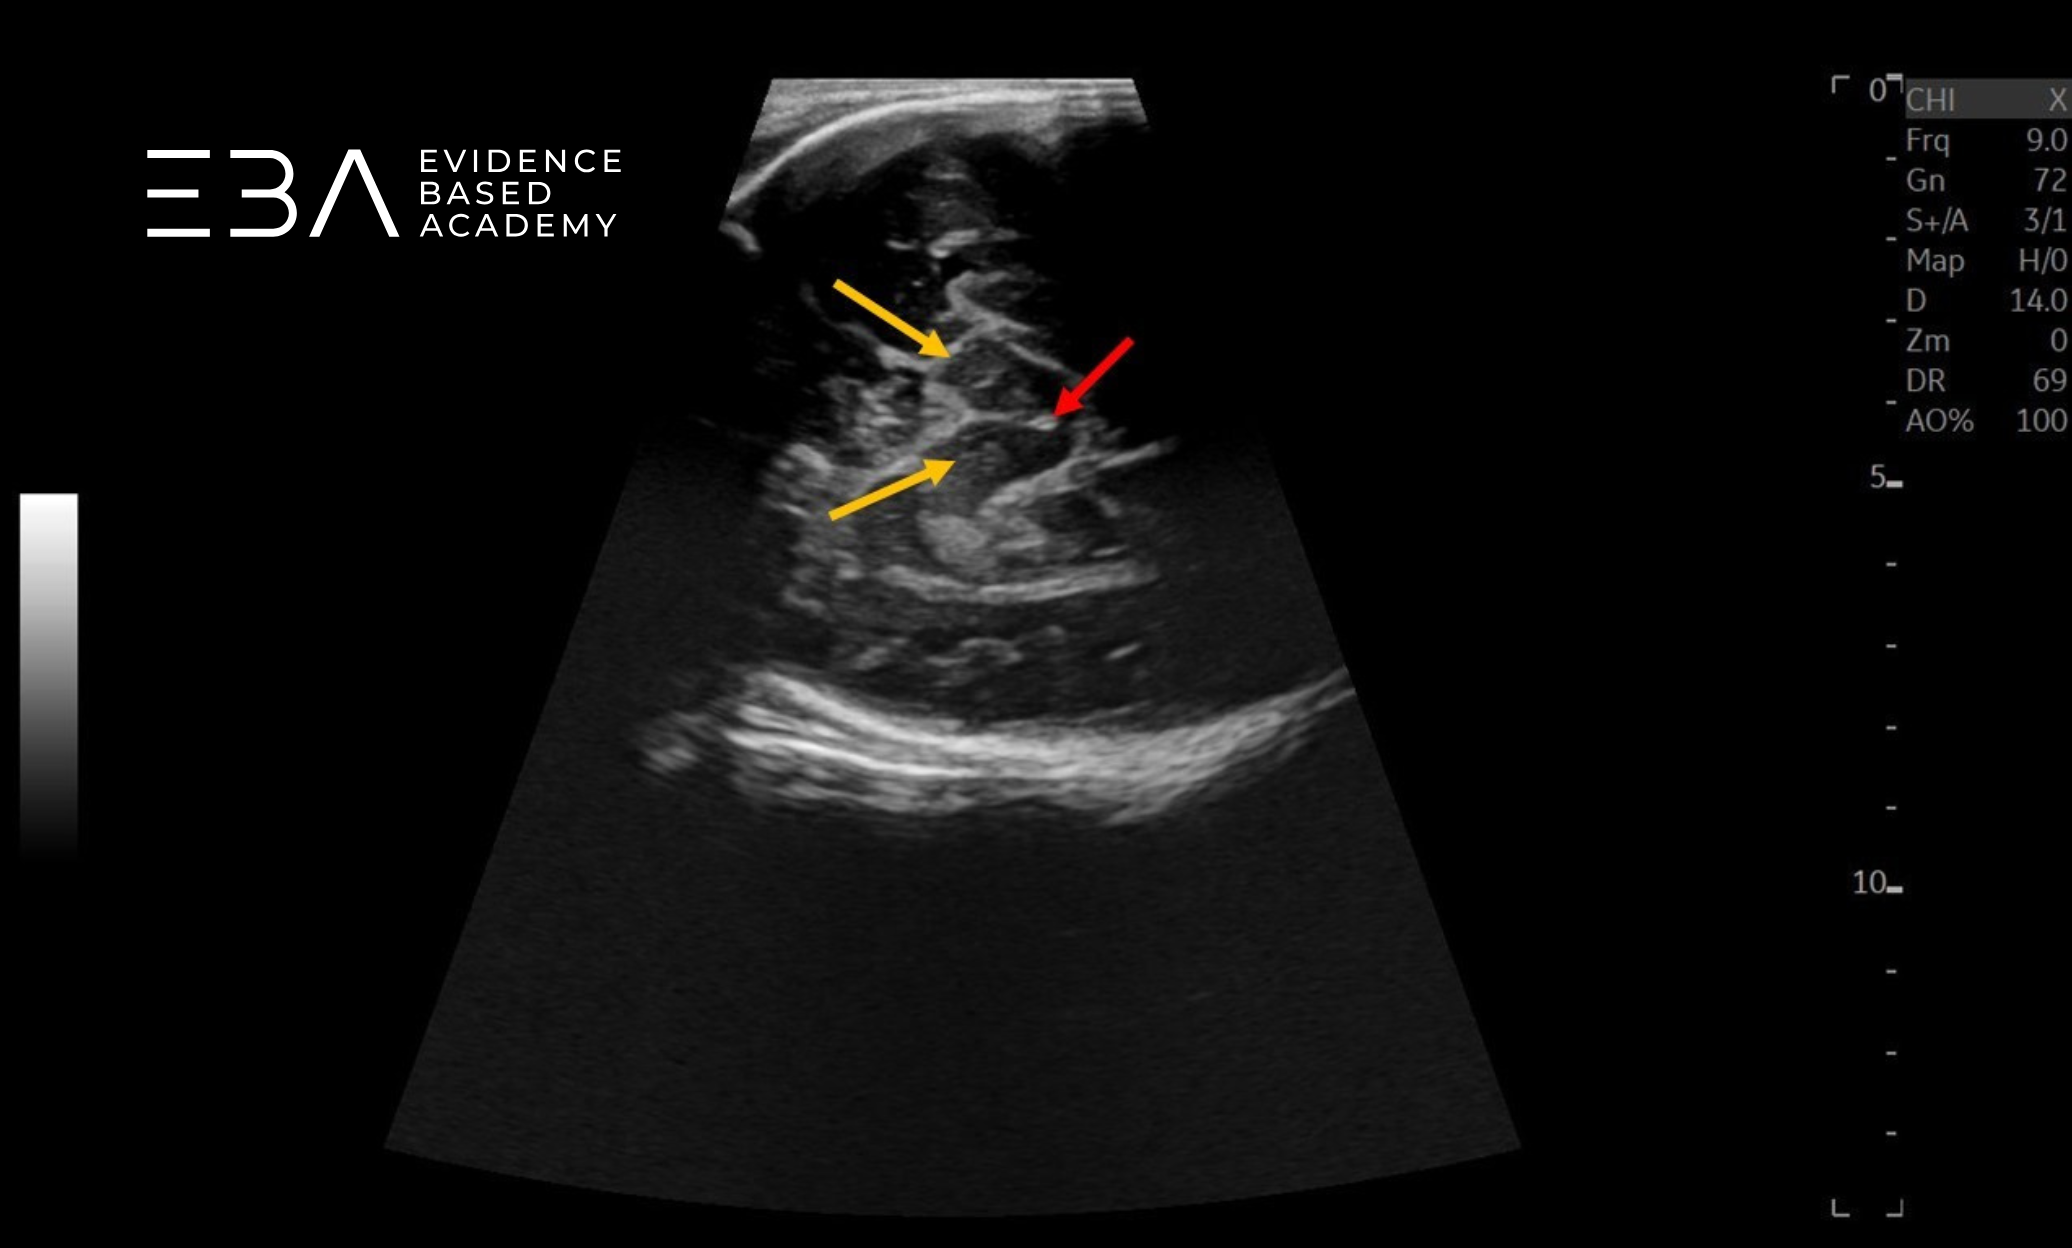

zdj. 5b

Głowica sektorowa – badanie przez łuskę kości skroniowej. Strzałkami zaznaczono konary mózgu.

Głowica liniowa – badanie przez łuskę kości skroniowej. Konary mózgu (żółte strzałki), wodociąg mózgu (czerwona strzałka).